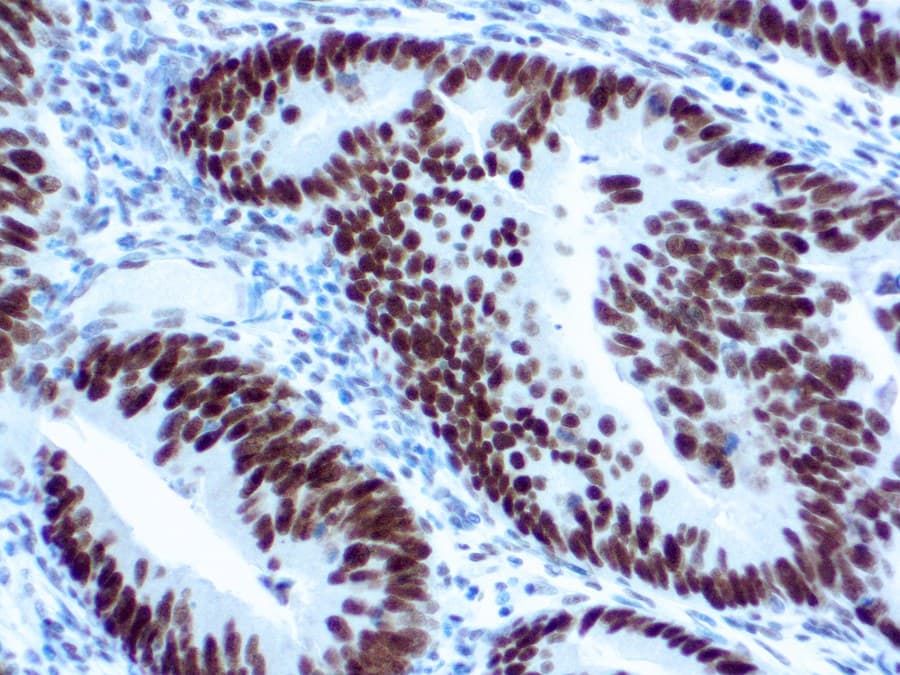

La evaluación inmunohistoquímica (IHC) de MLH1 es una herramienta diagnóstica estándar para tumores gastrointestinales. La pérdida de la tinción nuclear de MLH1 se correlaciona con un alto nivel de inestabilidad de microsatélites (MSI-H) e identifica tumores con deficiencia en la reparación de errores de apareamiento (dMMR). La IHC de MLH1 ayuda a estratificar tumores, predecir el pronóstico y guiar las pruebas moleculares, incluyendo el análisis de metilación del promotor de MLH1 o la secuenciación de línea germinal cuando se sospecha síndrome de Lynch. Su alta concordancia con las pruebas de MSI garantiza una identificación fiable del estado de MMR en cánceres colorrectales y gástricos.

- Se une específicamente a la proteína nuclear MLH1, permitiendo una detección precisa tanto en tejido tumoral como normal.

- La pérdida de tinción nuclear de MLH1 indica deficiencia de MMR; una tinción intacta refleja un sistema MMR competente (pMMR).